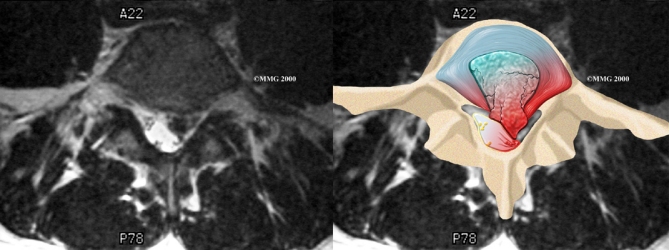

When more information is needed, your doctor may order (MRI). The MRI machine uses magnetic waves rather than X-rays to show the soft tissues of the body. It gives a clear picture of the discs and whether a herniation is present. Like the CT scan, this machine creates pictures that look like slices of the area your doctor is interested in. The test does not require special dye or a needle.